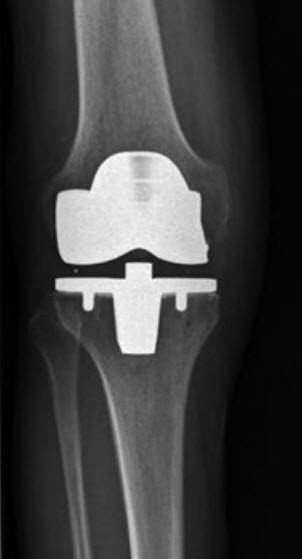

In der Schweiz werden pro Jahr rund 16 000 künstliche Kniegelenke implantiert. Der Einsatz einer Knieprothese ist somit eine Routineoperation und in der Regel sehr erfolgreich. Nachdem das künstliche Gelenk implantiert ist, wird es durch die eigenen Kniebänder stabil zusammengehalten. Die Kraft der eigenen Muskulatur sorgt dabei für eine freie Streckung und Beugung des Kniegelenks. Erfahren Sie hier generell mehr über den Einsatz von Knieprothesen.

Das Kniegelenk muss dazu vorn durch einen Hautschnitt von ca. 15 cm Länge eröffnet werden. Die abgenutzten Gelenksoberflächen werden nach einem speziellen Schnittplan bearbeitet und so für den künstlichen Oberflächenersatz vorbereitet. Die exakte Grösse und die Art der Prothese werden anhand der präoperativen Röntgenbilder und der Vermessung während der Operation ausgewählt. Das Kunstgelenk wird anschliessend meist mit Knochenzement im Knochen verankert.